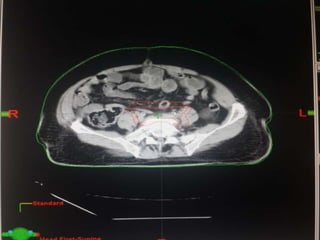

Our unit decide to treat:

 Prostate + S.V & prophylactic Pelvic LNs in

phase1

 Prostate + S.V phase 2

 Delineation of our unit illustrated in the

following slides:

Our unit decideto treat:  Prostate + S.V & prophylactic Pelvic LNs in phase1  Prostate + S.V phase 2  Delineation of our unit illustrated in the following slides: